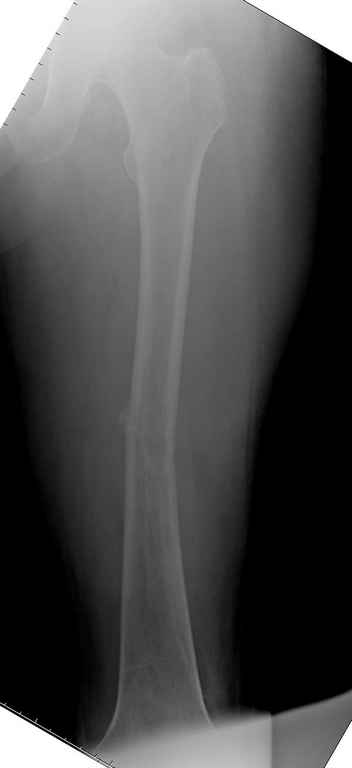

Здесь случай 66 летней пациентки со спонтанными болями в левой нижней конечности, обратилась в приемное, сделаны снимки бедра и КТ.

Патологический перелом бедра, конечность на вытяжении.

Да, я с достаточной для принятия решения степенью уверенности могу говорить, что это метастаз, потому что

-это не характерный возраст для осеосаркомы

-это не типичная локализация для остеосаркомы

-это не характерная рентгенкартина для остеосаркомы